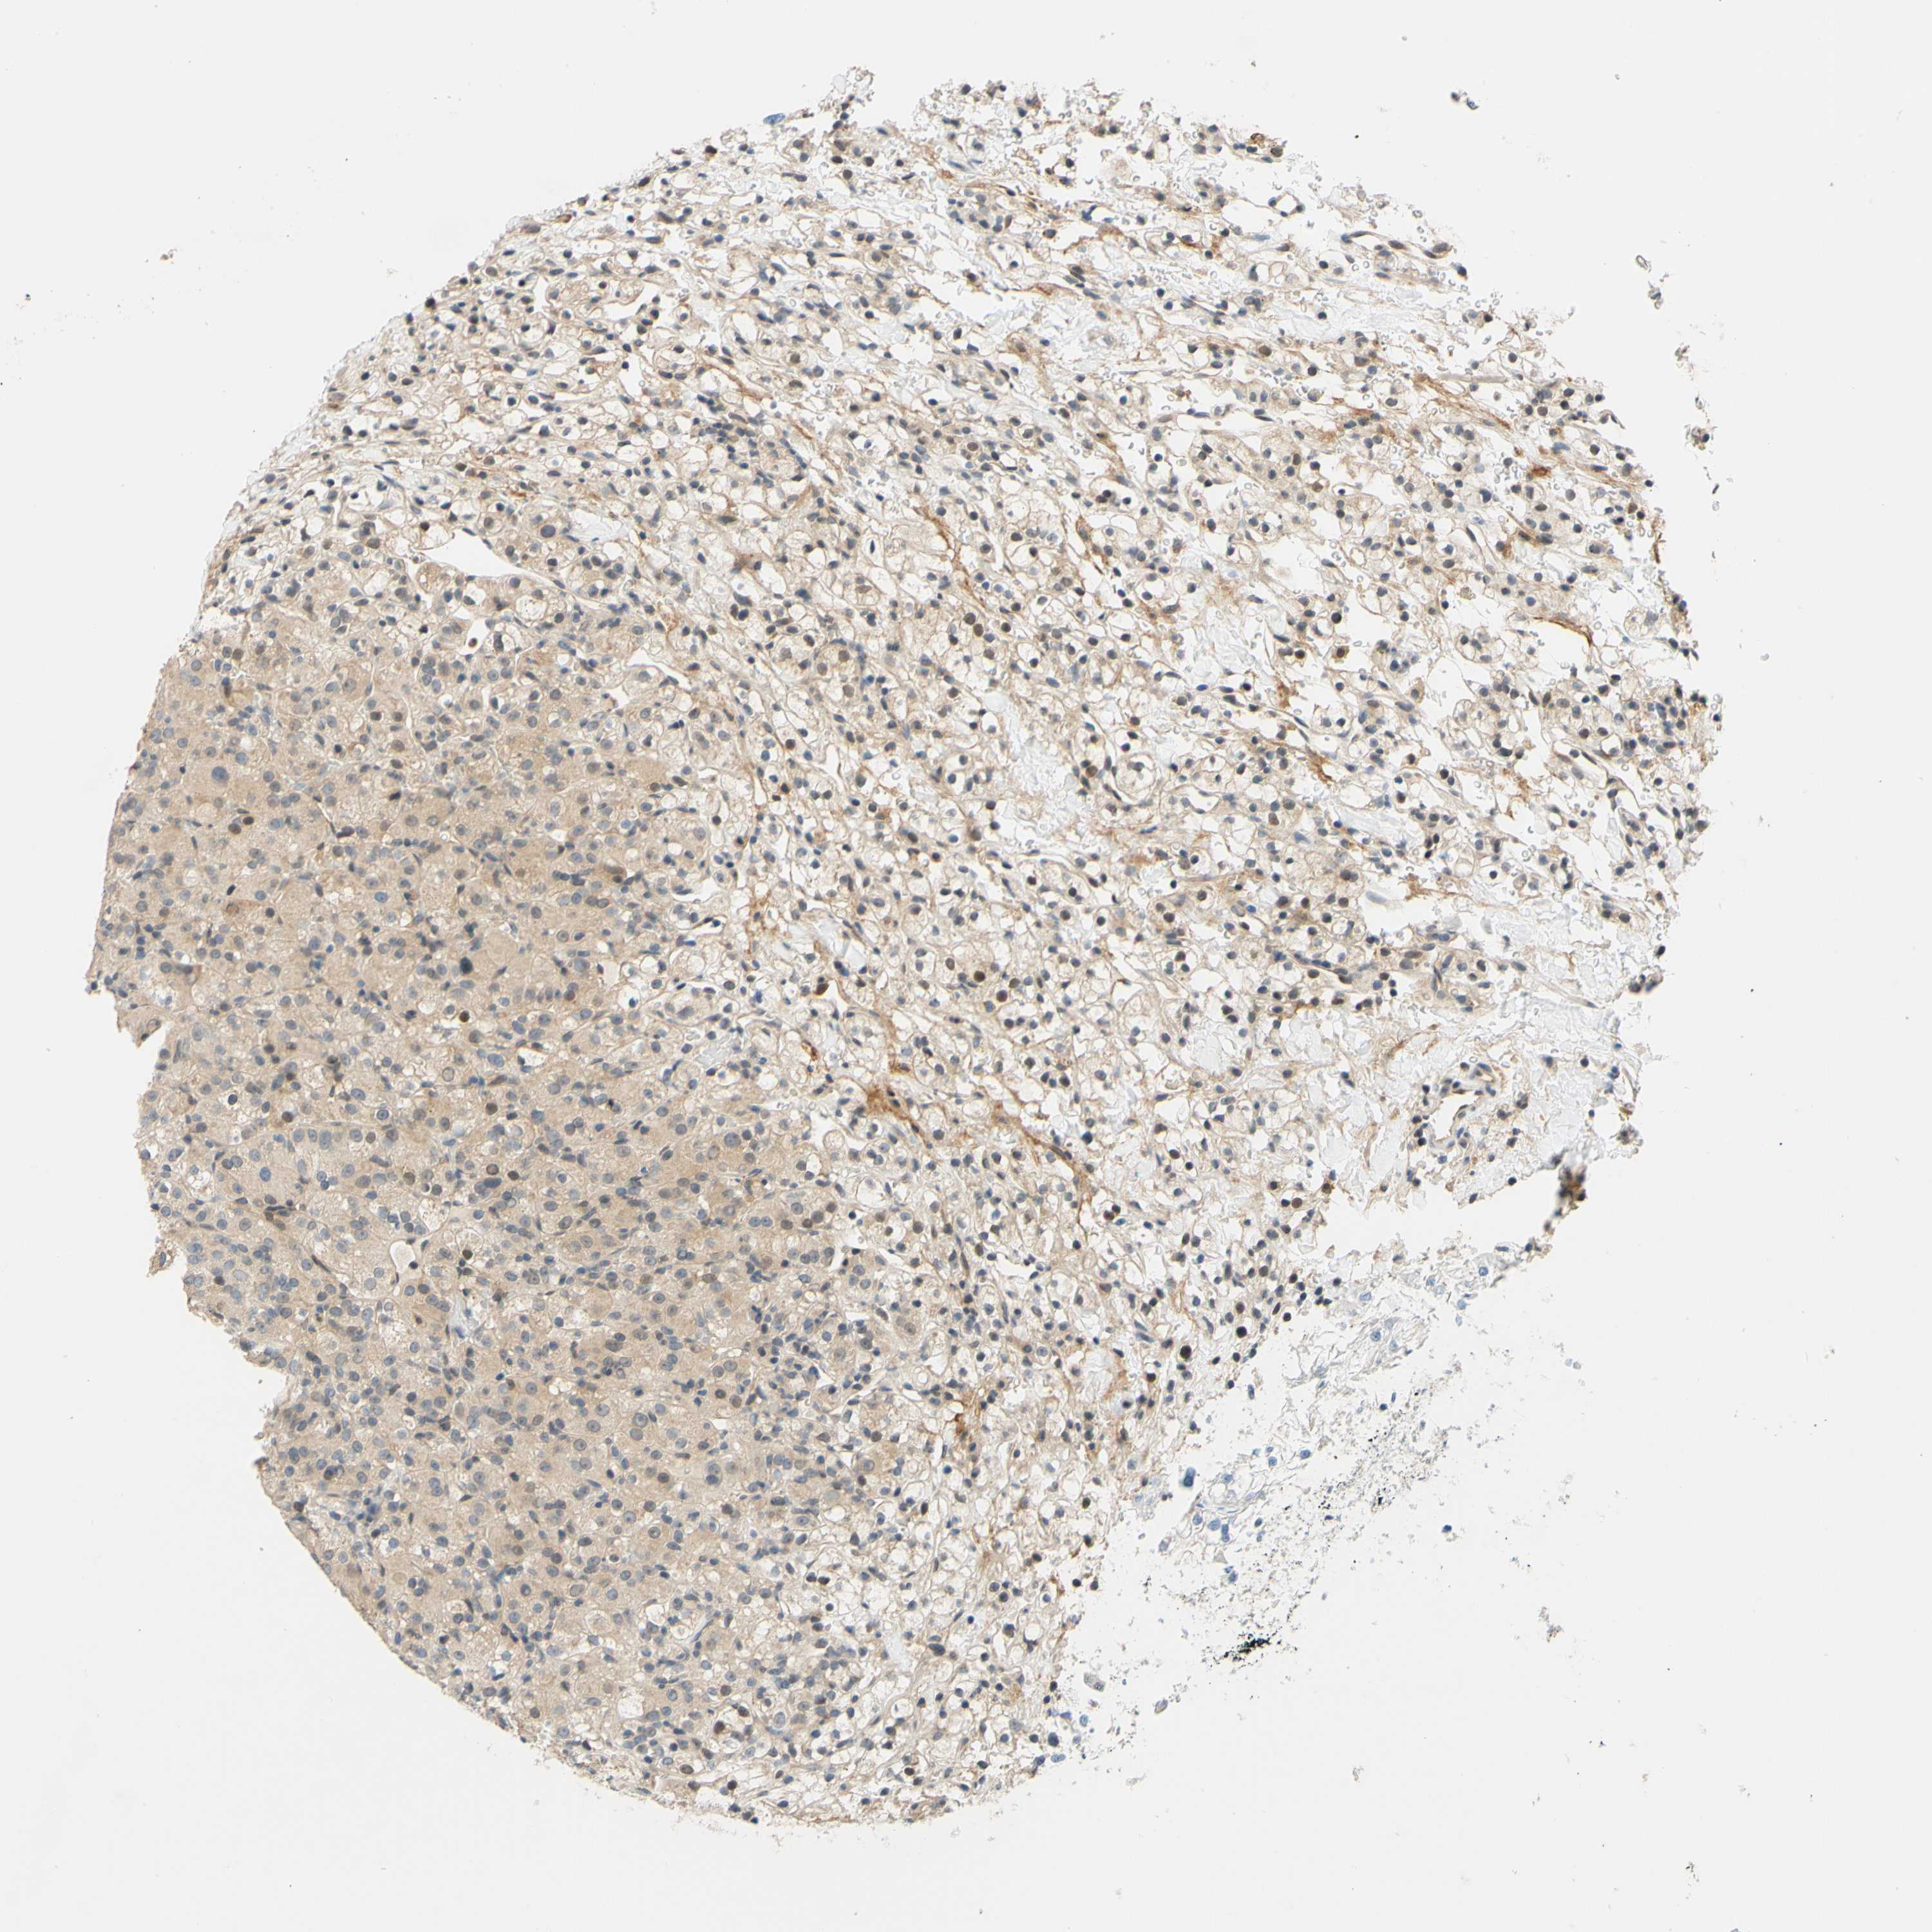

KIDNEY RENAL PAPILLARY CELL CARCINOMA (TCGA) - Interactive survival scatter ploti

The Survival Scatter plot shows the clinical status (i.e. dead or alive) for all individuals in the patient cohort, based on the same data that underlies the corresponding Kaplan-Meier plots. Patients that are alive at last time for follow-up are shown in blue and patients who have died during the study are shown in red.

The x-axis shows the expression levels (FPKM) of the investigated gene in the tumor tissue at the time of diagnosis. The y-axis shows the follow-up time after diagnosis (years). Both axes are complimented with kernel density curves demonstrating the data density over the axes. The top density plot shows the expression levels (FPKM) distribution among dead (red) and alive patients (blue). The right density plot shows the data density of the survived years of dead patients with high and low expression levels respectively, stratified using the cutoff indicated by the vertical dashed line through the Survival Scatter plot. This cutoff is automatically defined based on the FPKM cutoff that minimizes the p-score. The cutoff can be changed by dragging the vertical line or by entering a cutoff value in the square labeled "Current cut-off".

Under the Survival Scatter plot the p-score landscape (black curve; left axis) is shown together with dead median separation (red curve; right axis). Dead median separation is the difference in median mRNA expression between patients who have died with high and low expression, respectively. It is calculated as follows: median FPKM expression of dead patients with high expression - median FPKM expression of dead patients with low expression. This is intended to aid the user in visually exploring custom cutoffs and the associated p-scores and dead median separation.

Individual patient data is displayed and can be filtered by clicking on one or more of the category buttons on the top of the page. Categories describing expression level and patient information include: high, low, alive, dead, female, male and tumor stages. The scale of the x-axis can be toggled between linear and log-scale by clicking on the "x log" button. Mouse-over function shows TCGA ID, patient information and mRNA expression (FPKM) for each patient.

& Survival analysisi

Kaplan-Meier plots summarize results from analysis of correlation between mRNA expression level and patient survival. Patients were divided based on level of expression into one of the two groups "low" (under cut off) or "high" (over cut off). X-axis shows time for survival (years) and y-axis shows the probability of survival, where 1.0 corresponds to 100 percent.

C2CD2L is potential prognostic, high expression is favorable in Kidney Renal Papillary Cell Carcinoma (TCGA)

Best expression cut offi

Based on the FPKM value of each gene, patients were classified into two groups and association between prognosis (survival) and gene expression (FPKM) was examined. The best expression cut-off refers the FPKM value that yields maximal difference with regard to survival between the two groups at the lowest log-rank P-value. Best expression cut-off was selected based on survival analysis .

When clicking on this number, the vertical dashed line indicating cut-off, the interactive survival plot, and the Kaplan-Meier curve will be adjusted to show results based on the best expression cut-off.

: 5.23